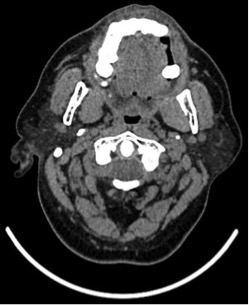

Durante la primera semana del mes de noviembre de 2018 le efectúan una TC de encéfalo y tórax con contraste EV (iopamidol); 36 horas más tarde, el paciente concurre a la consulta relatando dolor en región submandibular y cuello. Minutos después de finalizar el estudio comienza a percibir molestias mal caracterizadas en dichas zonas, notando edema progresivo y dolor. Al examen se constata tumefacción de región submandibular, retromandibular, cuello y piso de la boca, Lóbulos de las orejas desplazados hacia afuera, simétricos. Se palpan las seis glándulas salivales principales agrandadas de manera simétrica, dolorosas, sin rodetes eritematosos en las desembocaduras de los conductos salivales. Las glándulas submaxilares se palpan de forma ovoide y miden aproximadamente 6 cm de largo, se encuentran tensas y despiertan intenso dolor (Imagenes 1 y 2). El resto de las glándulas principales muestran similares características palpatorias. Niega fiebre y sus equivalentes.

Se solicita ecografía que demuestra glándulas salivales agrandadas sin alteraciones en el parénquima a destacar. Relata que unas pocas horas después del estudio contrastado, al comer, nota incremento del dolor y deformación en el cuello. Se efectúa tratamiento de hemodiálisis habitual y, durante el mismo, se administra hidrocortisona 500 mg por vía EV, AINE´s por vía oral. Una hora más tarde, refiere atenuación del dolor y se observa disminución generalizada del edema en forma simétrica. Se le indican AINE´s y antibacterianos. En la tercera semana muestra resolución parcial con tumefacción de las glándulas parótidas y submaxilar izquierda.(Imagines 3, 4 y 5)